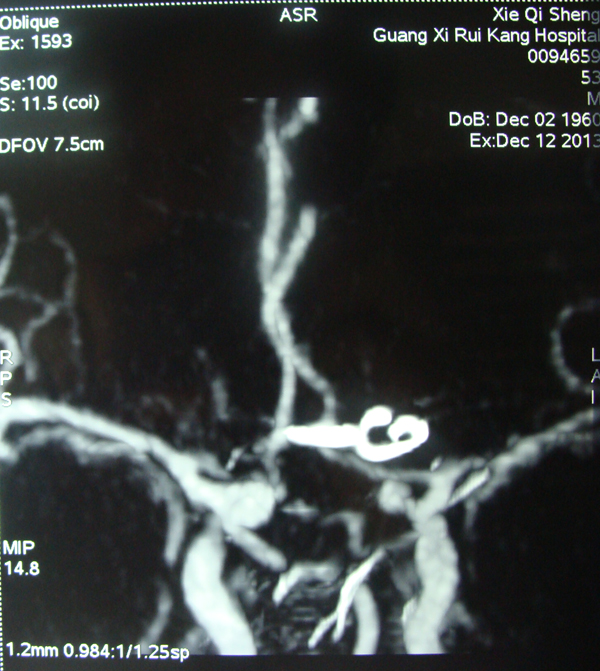

术前DSA侧位

动脉瘤位置。

前交通动脉位置